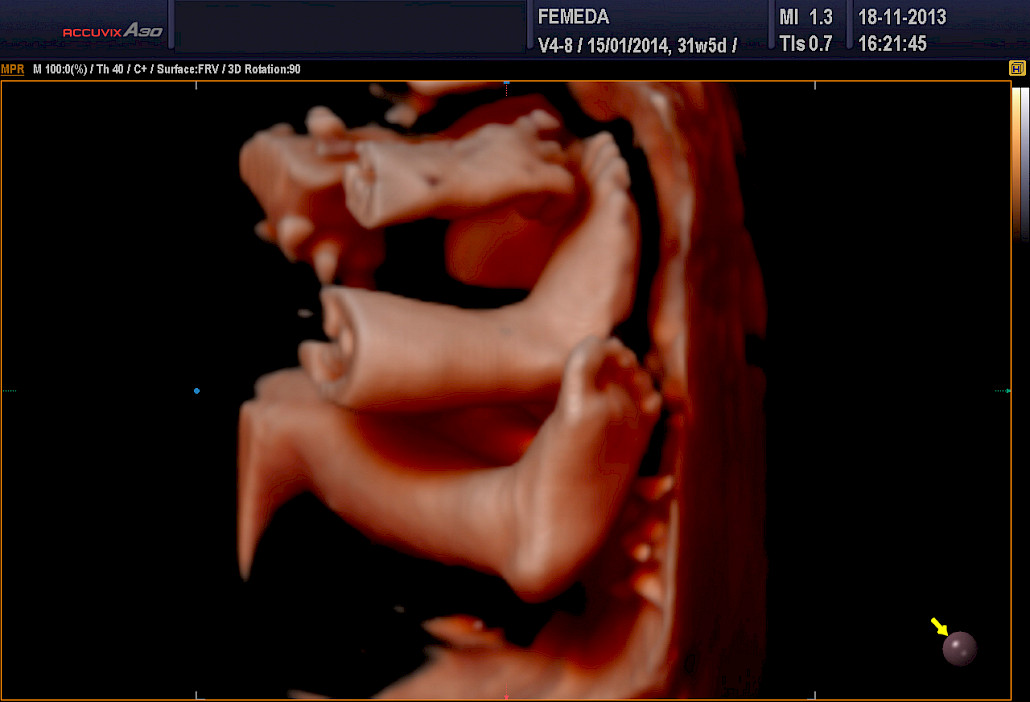

Ehdottomasti molemmat! 3D-tekniikalla tuotetaan staattista neulanterävää kolmiulotteista kuvaa. Se soveltuu sikiön kuvaamiseen, kun halutaan mahdollisimman tarkkaa ja korkealaatuista kuvaa. 4D-tekniikka on tarkoitettu erityisesti sikiön liikkuvaan ja kolmiulotteiseen kuvaamiseen.

Kuva Femedan 4D-ultraäänitutkimuksesta

3D ja 4D-tekniikat soveltuvat erityisen hyvin sikiön kasvojen anatomian tutkimiseen. Tutkimuksessa poissuljetaan mahdollinen huulihalkio ja kasvojen profiilissa esiintyvät muut poikkeamat, kuten liian pieni leuka. Samalla selvitetään korvien anatomia ja niiden sijainti. Tekniikan avulla selvitetään raajojen asennot, sekä sormien ja varpaiden lukumäärä ja niiden liikkuvuus. Lisäksi tutkitaan koko selkärangan rakenne ja suljetaan pois poikkeamat, kuten puuttuvat lapa- tai olkaluut.